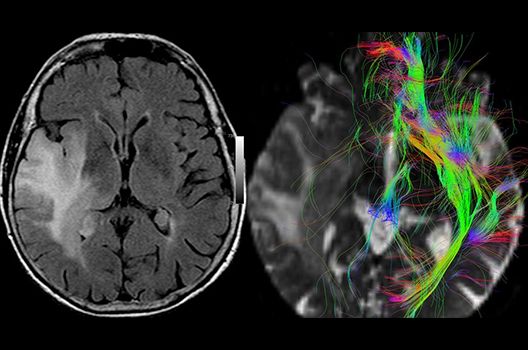

Magnetresonanztomographie

- Hochaufgelöste MR-Bildgebung (HR-MRT)

- Arterielle und venöse Angio-MRT

- MR-Protonenspektroskopie

- Funktionelle Bildgebung des Gehirns (fMRT)

- MR-Diffusionstensorbildgebung (Faserbahndarstellung/fiber tracking)

Die Schwerpunkte in der MR-Forschung liegen in der multiparametrischen und funktionellen Bildgebung bei onkologischen und anderen, neuroradiologischen Fragestellungen und umfassen die Anwendung modernster MR-Verfahren sowie die Untersuchung an Hochfeld-Geräten.

Die Magnetresonanztomographie (MRT) ist ein Verfahren, bei dem durch magnetische Kräfte Bilder des Körperinneren angefertigt werden. In der Neuroradiologie können manchmal kleinste Veränderungen schwere Folgen haben; daher forschen wir an der Entwicklung hochauflösender MRT-Sequenzen, mit denen diese Prozesse und auch einzelne Nervenfaserbahnen sichtbar gemacht werden können. Darüber hinaus sind bei vielen Erkrankungen des Gehirns die Blutgefäße betroffen. Daher arbeiten wir an der Neu- und Weiterentwicklung von MRT-Sequenzen zur Darstellung der Blutgefäße und zur Blutflussanalyse (sog. „Angio-MRT“). Einen besonderen Forschungsschwerpunkt unserer Klinik stellen die MR-Protonenspektroskopie und die funktionelle MRT dar, mit denen die Analyse einzelner chemischer Substanzen im Hirngewebe oder die Darstellung ausgewählter Hirnfunktionen möglich ist.